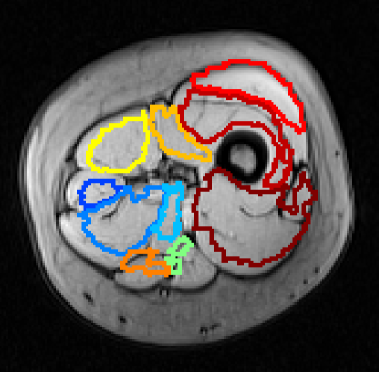

Refer to caption

Figure 5: Labeled skeletal muscle segmentation results.

When the recall rate is lower but precision in increased, muscle labels are, generally, placed correctly, despite the total segmented muscle area being slightly affected (Figs. 5(c) and (d)). Muscles with a smaller cross-sectional area in most of the used MRI, such as the Sartorius or the Rectus femoris, tend to be unrecognized on the labeled segmentation results if true positive recognition decays in those regions.

Despite the disadvantages of this method, the obtained results suggest that it may perform well in a variety of different scenarios, particularly in cases with more intermuscular tissue or near articulations, where the muscle region of interest is more disperse. Nevertheless, it should be noted that an adequate selection of reference MRI for the atlas construction is critical for a consistent accuracy of this approach, given the variations on muscle geometry and relative positioning, which is quite stable in consecutive slices.